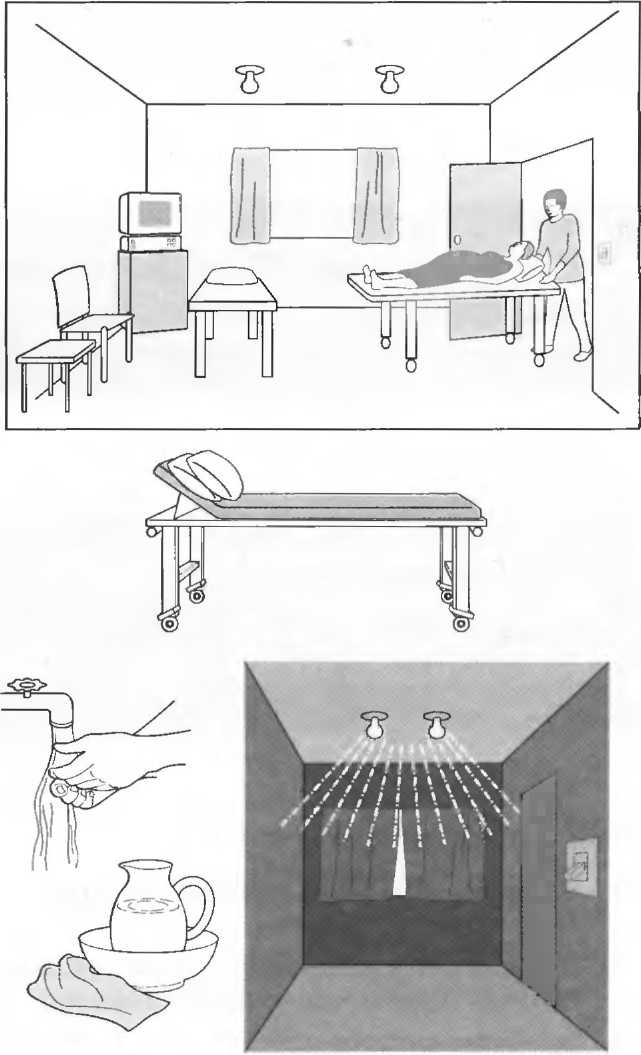

Оборудование кабинета ультразвуковой диагностики

Не требуется радиационной защиты.

От медицинской диагностической ультразвуковой аппаратуры нет опасного радиационного излучения, нет необходимости в специальном покрытии для стен кабинета. Тем не менее в комнате должно быть сухо и не должно быть пыли.

Кабинет должен быть достаточно большим, чтобы вместить ультразвуковой аппарат, кушетку, кресло и маленький или письменный стол. Он должен быть достаточно большим, для того чтобы ввезти каталку с пациентом и переложить его на кушетку. В комнате должен быть отдельный вход для соблюдения конфиденциальности исследования.

Для удобства пациента кушетка должна быть ровной, но мягкой, с поднимаемым головным концом. Если кушетка на колесиках, то нужны хорошие фиксаторы. Должны быть две ровные подушки. Кушетка должна легко мыться.

В комнате должна быть раковина, чтобы помыть руки, по возможности, в кабинете также должна иметься питьевая вода, рядом должен находиться туалет.

В кабинете должно быть окно или другой источник вентиляции и освещения, желательно с неярким светом или должен существовать способ изменения яркости освещения. Яркий солнечный свет должен быть экранирован или могут использоваться занавески. Если комната слишком светлая, изображение на экране монитора будет трудно видеть.

Какие необходимы электрические розетки?

Специального источника питания не требуется: нужна стандартная розетка, например на 220 В на 5 А или 110 В на 10 А. Не требуется специальной электрической проводки. В прилагаемом описании прибора необходимо уточнить технические характеристики. Важно, чтобы закупаемое ультразвуковое оборудование могло работать от обычных источников питания, а компания, продающая оборудование, должна проверить и подтвердить это в описании.

Основные источники питания во многих госпиталях и клиниках, особенно в развивающихся странах, значительно различаются по вольтажу и частоте тока. При наличии слишком больших колебаний в сети ультразвуковая установка может быть повреждена или может плохо работать. В этом случае необходимо закупить стабилизатор напряжения. Это необходимо определить еще до приобретения оборудования.